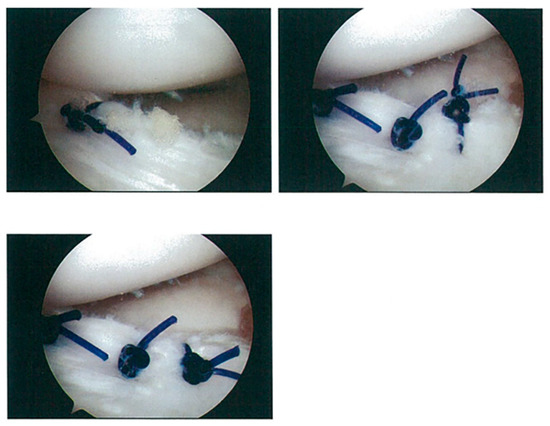

2.2. Surgical Procedure